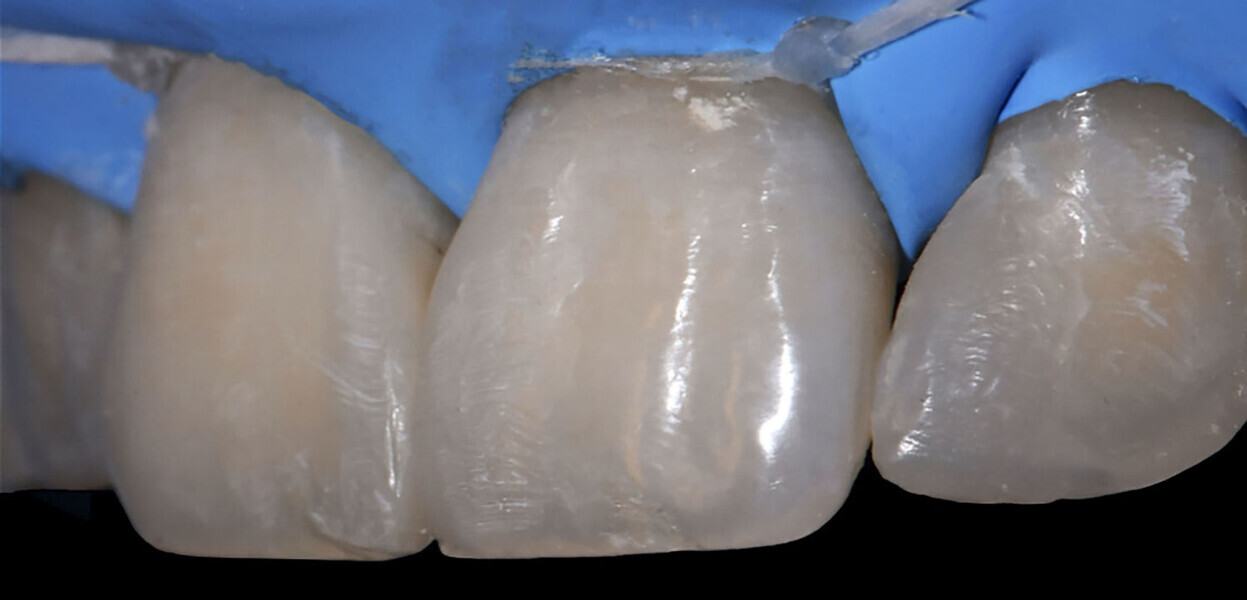

Timeline of treatment steps Having completed the assessment steps, it was possible to proceed with the operative steps for the aesthetic and functional management of the factors affecting the smile line.5,6 As a first step, a dental dam was positioned (Fig. 4).7 Conditioning of the enamel and bonding then followed. Acid etching (Vococid, VOCO) of the interproximal surfaces of teeth #11 and 21 as well as of the mesial surface of tooth #12 was performed for 20 seconds (Fig. 5). The etching agent was then aspirated and rinsed off with water for 15–30 seconds and the surfaces dried with a gentle air stream to obtain a chalky white opaque appearance (Fig. 6). The universal bonding agent (Futurabond U, VOCO) was applied to and rubbed on the conditioned enamel surfaces (Fig. 7), and the solvent was carefully evaporated using compressed dry air for at least 5 seconds so that the layer of adhesive became thin, immobile and shiny. The bonding agent was then light polymerised for 10 seconds with a high-power LED lamp (Celalux 3, VOCO).

Reconstruction of the contact point mesial to tooth #12 and distal to tooth #11 A wedge and matrix system (Ena Matrix, Micerium) was inserted. To ensure good visual control and proper polymerisation on tooth #12, a transparent matrix was chosen (Fig. 8). After the application of an initial layer of packable composite, a nano-hybrid very low-viscosity flowable composite (GrandioSO Light Flow, VOCO) was used to ensure proper sealing of the conditioned enamel (Fig. 9).

Closure of the diastema between teeth #11 and 21 The operative steps chosen to close the space between teeth #11 and 21 were carried out using a technique we adapted involving the simultaneous use of two appropriate sectional matrices (Fig. 10) applied sequentially as described next. This was done drawing inspiration from scientific work aiming to restore, in a single clinical session, the natural smile line of patients with periodontal disease8 or to manage the matrices in a versatile manner.9

First of all, the first metal sectional matrix (thickness of 60 µm) was positioned vertically and fixed with a wedge (Ena Matrix). To obtain a clinical preview of the contact point of the central incisors,10 we then added a second matrix, again in a vertical position, with the intention of defining the emergence profile when performing the cervical restoration. It acts passively on the wedge and pushes it against the interdental papilla. Having stabilised the wedge and matrix system, the first layer of sculptable composite (Admira Fusion, Shade A2; VOCO) was applied to the mesiovestibular wall of tooth #11 using the median landmark created by the physical contact generated between the two matrices. Not too much material should be applied in the vestibular-palatal direction. This system offers the advantage that, once a matrix has been removed, the special wedge can be left in place for haemostatic purposes ready for the insertion of another matrix of the same system. The sectional matrix was removed from the wall of tooth #11 while maintaining the previously achieved anatomical limits (Fig. 11). We then applied a composite increment to the mesial wall of tooth #21, as here the matrix was still in place.11